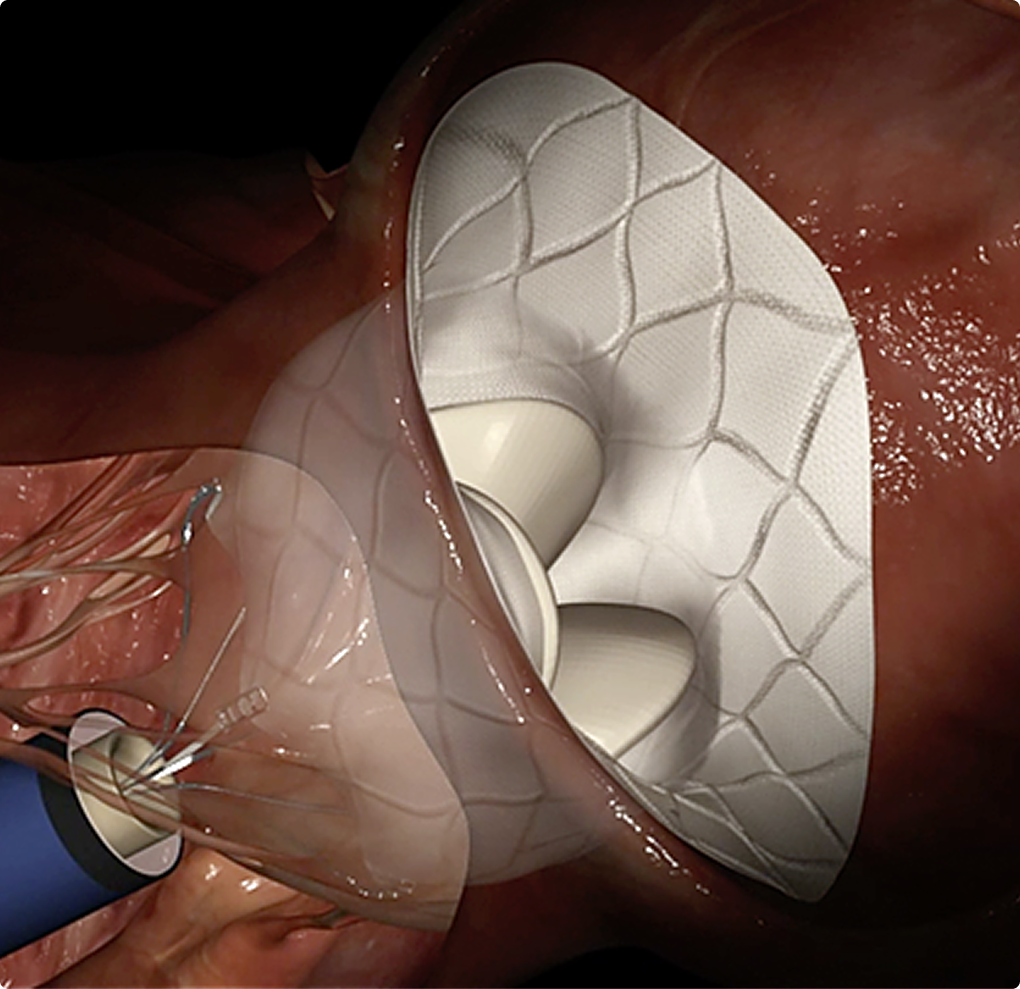

Advancing world-first breakthroughs, faster

World first breakthroughs aren't designed to sit on the lab bench forever. They need to be in the hands of doctors and patients - saving lives and transforming outcomes. We help you get there.

Medical innovations are not one-size-fits-all, so why should your clinical trials be? At Mobius, our team uses their deep expertise to develop a clinical trial strategy tailored for you.